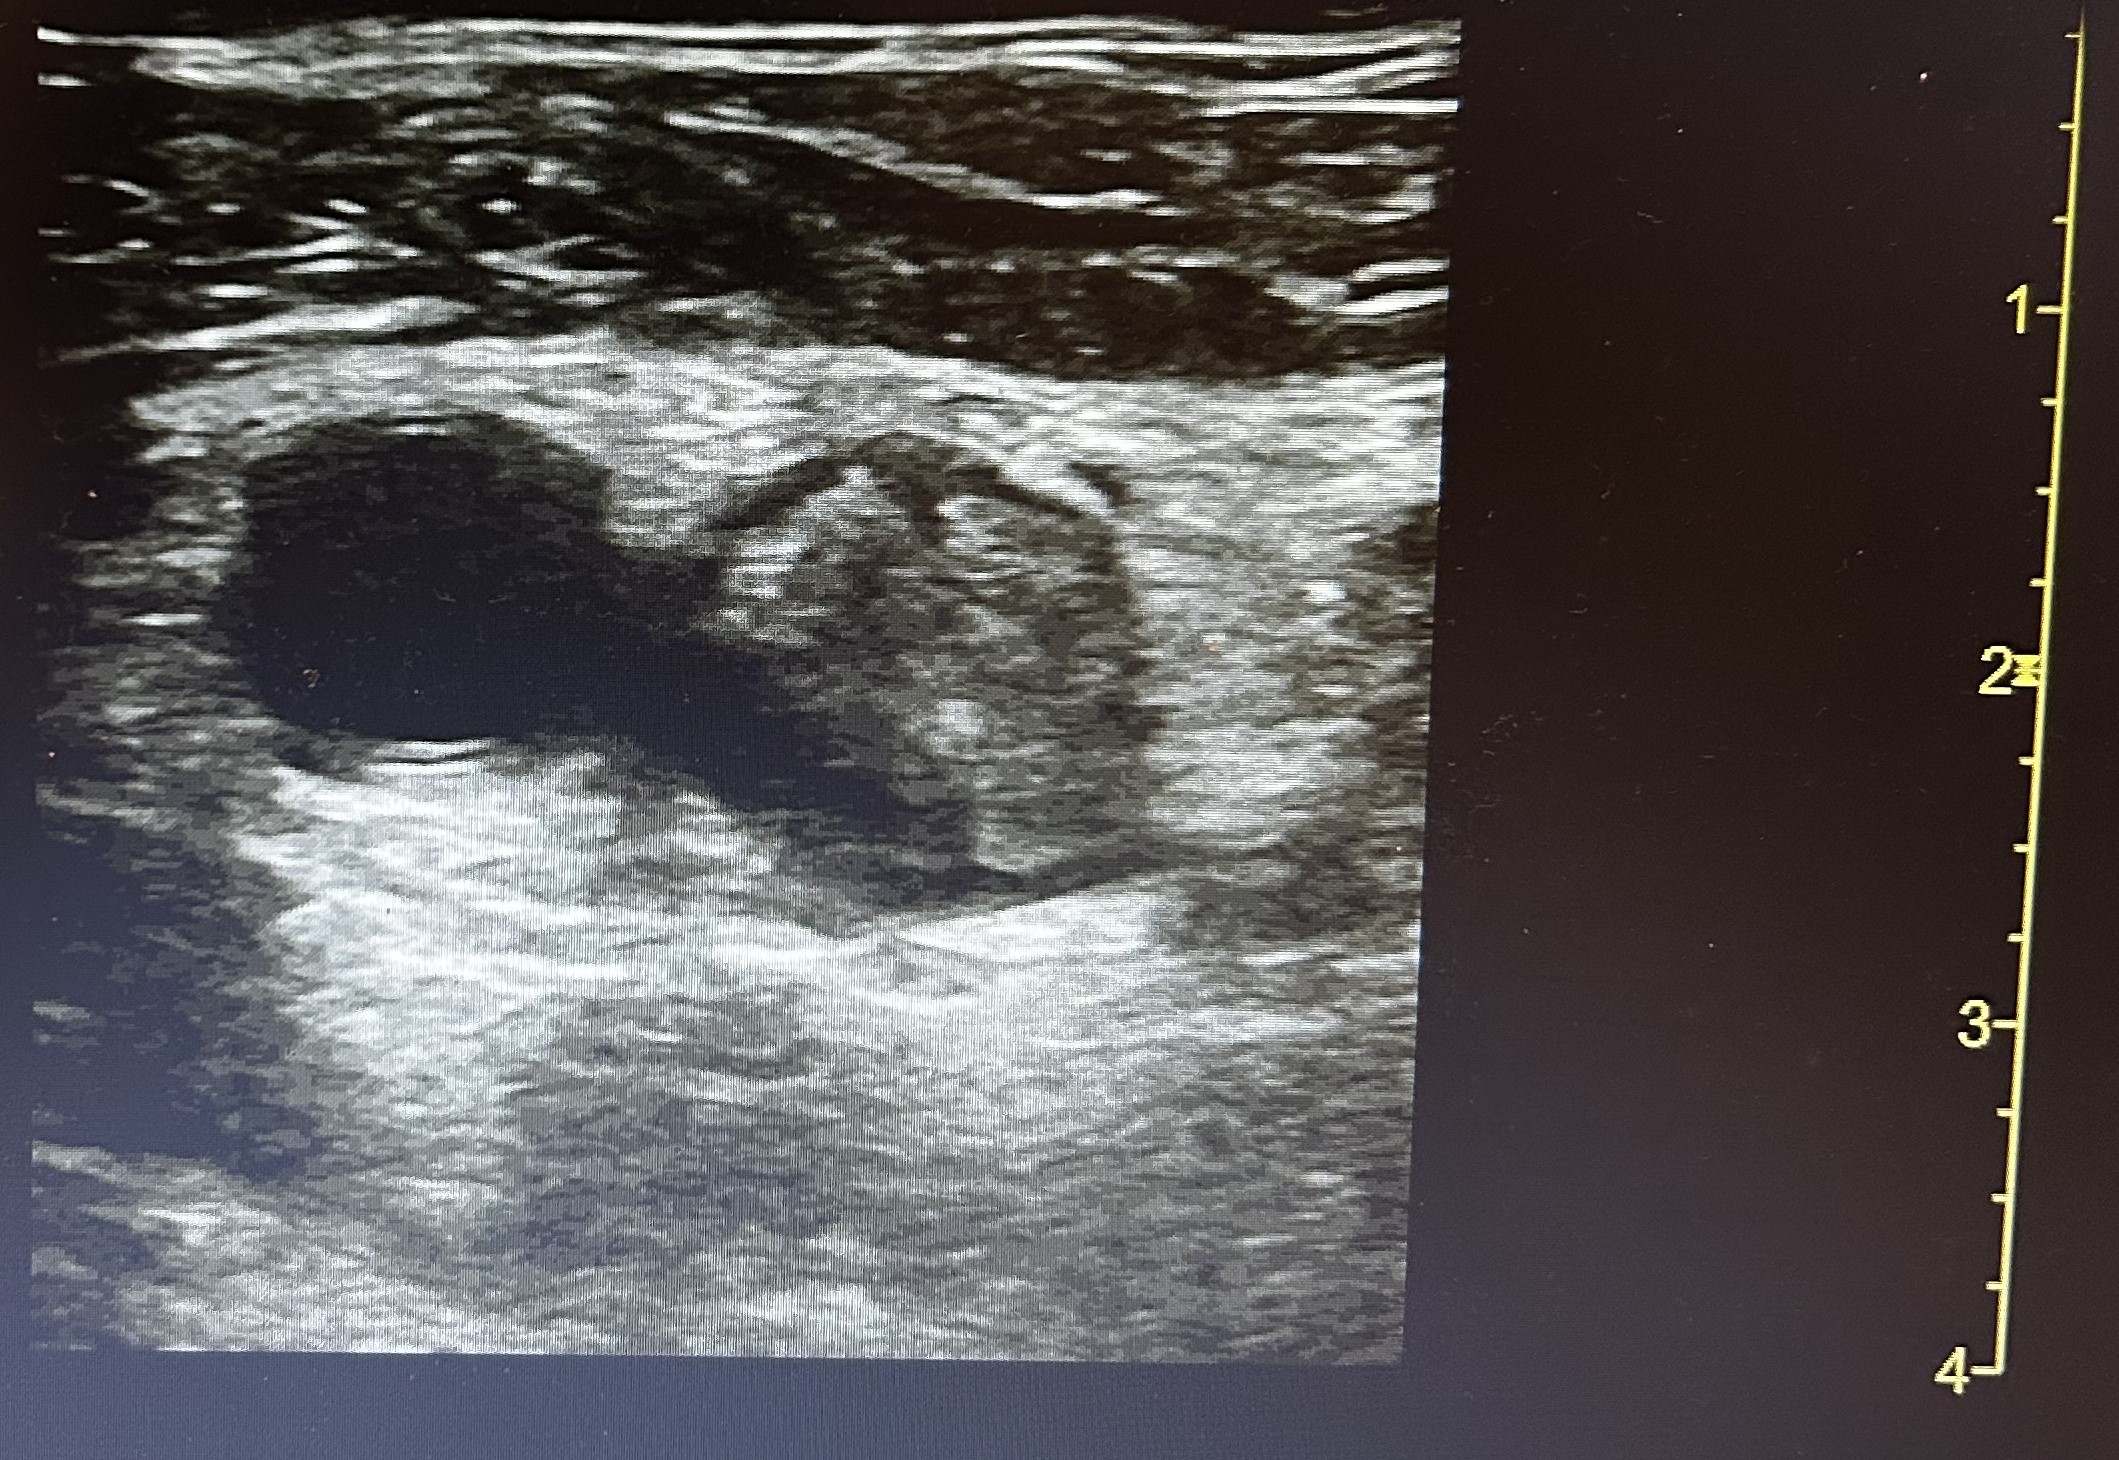

Ante cuadro sugerente de trombosis venosa se realiza ecografía-doppler venoso de la extremidad afectada objetivándose extensa Trombosis venosa profunda con afectación desde vena iliaca externa hasta territorio infrapoplíteo.